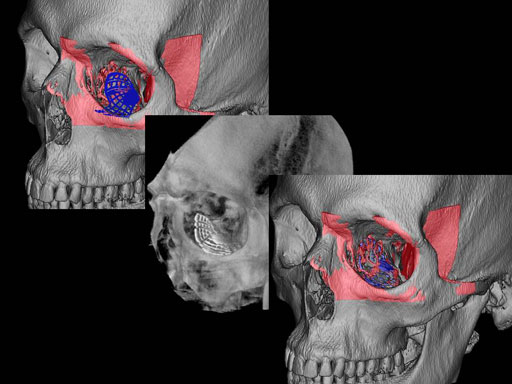

Furthermore, as orbital floor fractures are quite frequently associated with medial wall fractures; anatomic restoration especially in the transition zone between both wall is a demanding procedure. As described by B. Hammer, the orbital floor has an initial shallow convex section behind the rim, then inclines upward behind the globe, and inclines upward to meet the medial wall, creating a distinct bulge behind the globe. These convex curves of the medial wall and floor create a postbulbar constriction of the orbital cavity, which must be reconstructed when the orbit is rebuilt following fractures. Treatment is directed at precise anatomical reconstruction of orbital shape and volume in order to restore the correct position of the eye. To provide surgeons with an adequate implant that addresses the requirements of two wall acute orbital fractures or for secondary reconstruction of enophthalmos and dystopia, a new series of preformed orbital plates was developed for the new orbital matrix system.

Unlike the existing two-dimensional mesh implants, the geometry of the new preformed plates will be adequate to match the individual anatomic situation of the patient in almost any case. However, the mesh parts can be individually adjusted if necessary. In these cases the solid part in the central posterior area needs to remain untouched. Areas of the orbit that do not require a bridging can be spared out by trimming the implant along the designated cutting lines in the height of the medial wall and/or length of the orbital floor area. The lateral anterior part of the plate is intentionally pre-bent higher than the orbital rim anatomy to allow free plate movement during plate positioning.

The Preformed Orbital Plates are indicated for trauma repair and reconstruction of fractures of the orbital floor, medial orbital wall or combined fractures of floor and medial wall. It should be noted that in three-wall fractures where the lateral wall is also involved, a second orbital implant, ( i. e. the mesh plate) must be used in addition to the pre-formed orbital plate.

Implant placement according to the orbital landmarks

1 Orbital rim, 2 Inferior orbital fissure, 3 Posterior orbital ledge, 4 Transition between the medial wall and orbital floor, 5 Optic canal, 6 Lacrimal fossa

30 year old male patient with fracture of left orbital floor and medial wall.

Provided by Dr Dr Marc C Metzger, Freiburg, Germany.